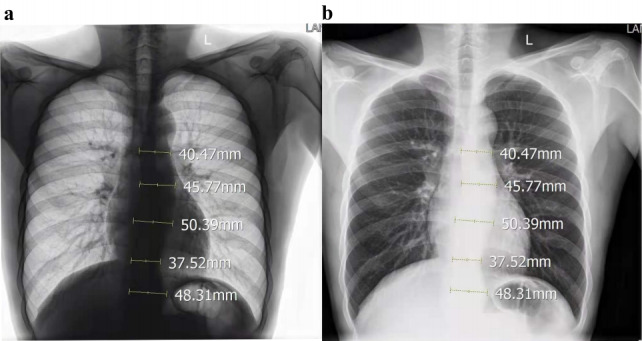

Case report: A young male patient presented with acute chest pain following strenuous exertion. Initial outpatient evaluation, including complete blood count (CBC), liver function tests (LFTs), renal function tests (RFTs), cardiac enzymes, and chest X-ray (CXR), yielded nondiagnostic results, leading to his discharge with analgesics. Three days later, during a national holiday when outpatient clinics were closed, the patient returned to the emergency department (ED) with persistent chest pain. A meticulous review of the initial CXR by the emergency physician revealed mediastinal widening (measuring 8.5 cm) and an abnormal contour of the aorta. Subsequent emergency computed tomography angiography (CTA) confirmed the diagnosis of a Stanford type B aortic dissection.